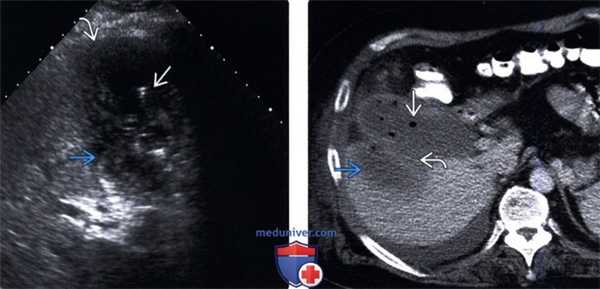

(Левый) На поперечном УЗ срезе у пациента с эмфиземой и перфорацией желчного пузыря определяется разрыв стенки, отмечается исчезновение эхогенной полосы слизистой. В просвете желчного пузыря определяются газ и скопление перипузырной жидкости.

(Правый) При КТ с контрастным усилением на аксиальной томограмме у этого же пациента наблюдаются признаки острого эмфизематозного холецистита с перфорацией. Виден фокальный разрыв стенки желчного пузыря. Также определяется газ в просвете пузыря и в перипузырном пространстве.